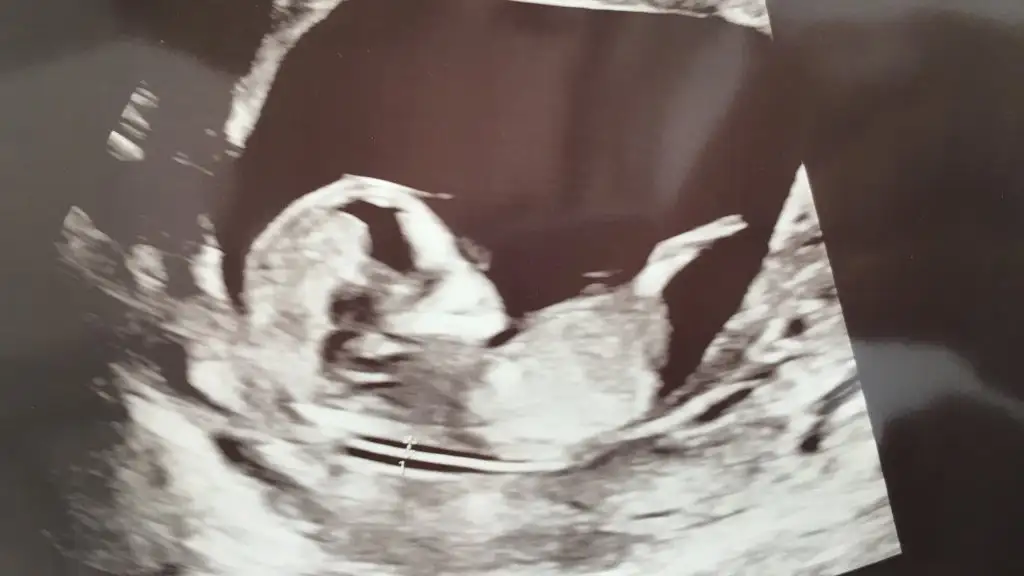

Canım bu ultrasona bakabilir misin belki bir fikrin olabilir 😊 Bu arada 11+5 karından çekildi Pasha22 Pasha22

• F279E3E8-300A-4D53-A028-266A659A3A33.webp

F279E3E8-300A-4D53-A028-266A659A3A33.webp

18,4 KB · Görüntüleme: 93